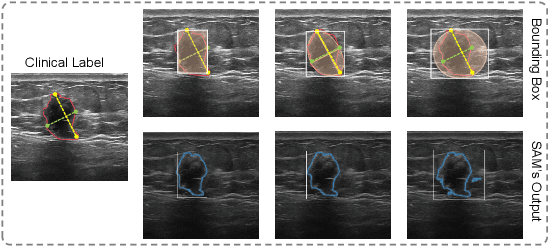

Abstract:Automated nodule segmentation is essential for computer-assisted diagnosis in ultrasound images. Nevertheless, most existing methods depend on precise pixel-level annotations by medical professionals, a process that is both costly and labor-intensive. Recently, segmentation foundation models like SAM have shown impressive generalizability on natural images, suggesting their potential as pseudo-labelers. However, accurate prompts remain crucial for their success in medical images. In this work, we devise a novel weakly supervised framework that effectively utilizes the segmentation foundation model to generate pseudo-labels from aspect ration annotations for automatic nodule segmentation. Specifically, we develop three types of bounding box prompts based on scalable shape priors, followed by an adaptive pseudo-label selection module to fully exploit the prediction capabilities of the foundation model for nodules. We also present a SAM-driven uncertainty-aware cross-teaching strategy. This approach integrates SAM-based uncertainty estimation and label-space perturbations into cross-teaching to mitigate the impact of pseudo-label inaccuracies on model training. Extensive experiments on two clinically collected ultrasound datasets demonstrate the superior performance of our proposed method.